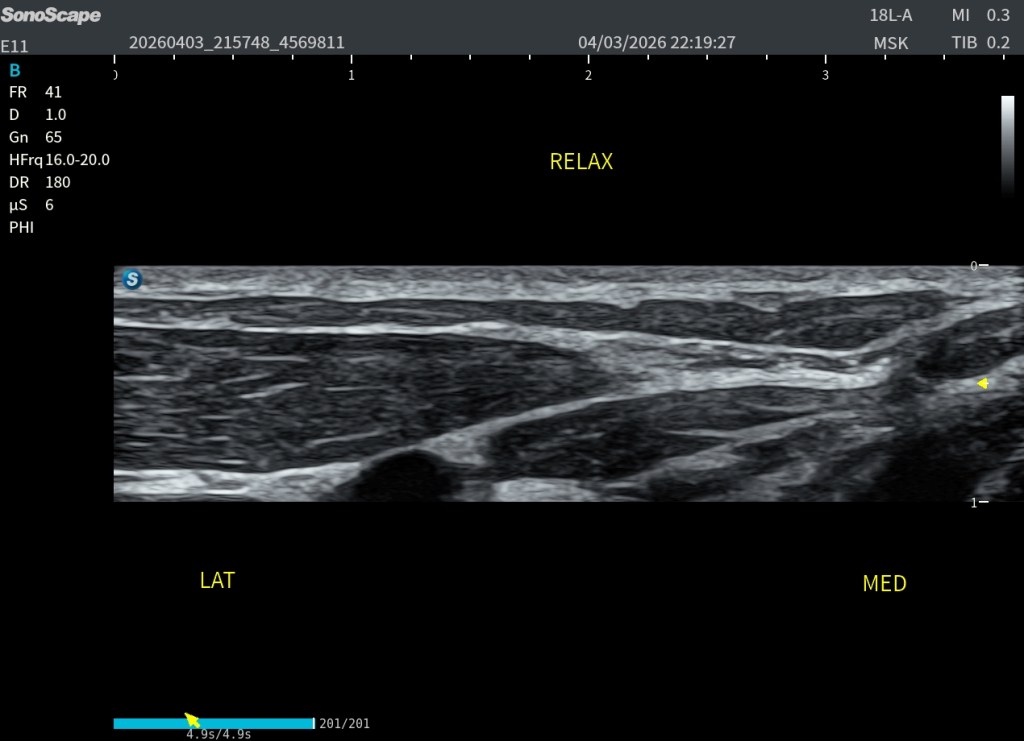

Una vez optimizada la técnica, el platisma se reconoce como una estructura muy fina, hipoecogénica, de aspecto plano y continuo, sin un patrón fibrilar tan evidente como el de otros músculos, repito muy variable en su presentación. Se localiza entre la grasa subcutánea, que es más ecogénica, y los planos musculares profundos, que presentan una arquitectura más definida. Podemos identificarlo como entre dos laminas hiperecogénicas. Como un bocadillo. El ECM siempre nos va a ayudar, un buen libro de anatomía del cuello al lado, tambien.

Un aspecto especialmente útil para su reconocimiento es su comportamiento dinámico. En el caso que da soporte a este post, al solicitar la contracción al paciente, se observa que las fibras laterales tienden a engrosarse, mientras que las fibras mediales se aplanan.

Desde el punto de vista clínico, el Platisma tiene un papel clave como referencia anatómica. Una identificación incorrecta puede llevar a errores en la localización del plano superficial, a una interpretación inadecuada de la profundidad de lesiones y a posibles fallos en procedimientos ecoguiados. Siempre identicar bien, región lateral y medial, estudiar en relajación y usar siempre estudio comparativo.